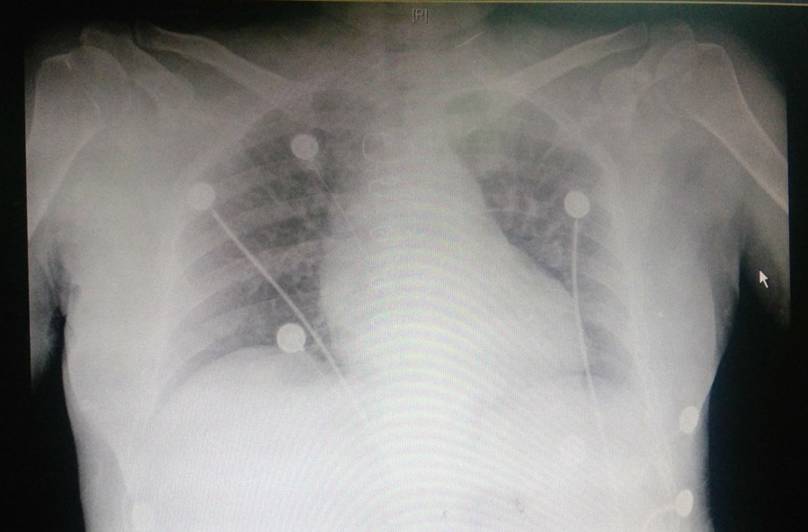

两肺纹理偏重,未见实变,主动脉结偏宽 ,肺动脉段平直,左心圆隆.